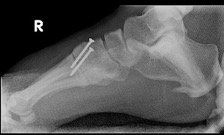

Surgery for midfoot arthritis ranges from simple to more complex procedures. Surgery may involve a “clean-up” of the joint by removing damaged cartilage and bone spurs, resection of a part of the joint, fusion (stiffening) of one or more joints. Medical imaging, such as x-rays and MRIs are usually obtained prior to surgery to determine the extent of the injury and to plan for the proposed surgery.